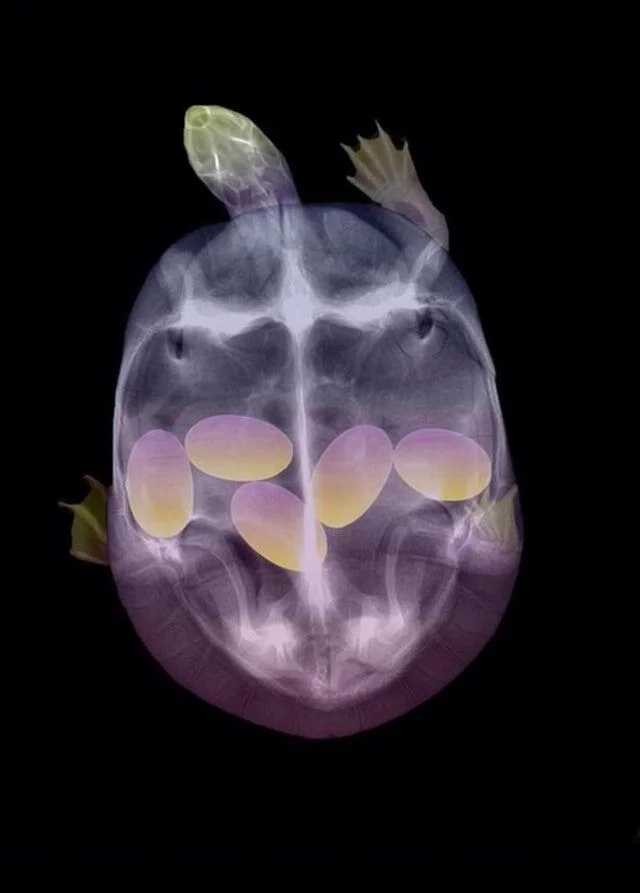

11. Раскрашенный снимок беременной черепахи